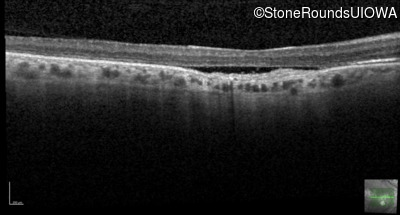

Optical Coherence Tomography - Right - 20/100

Exemplar / OCT Stack

OCT Stack

Optical Coherence Tomography - Left - 20/100

Infrared Fundus Photograph - Right - 20/100

Exemplar

Infrared Fundus Photograph - Left - 20/100